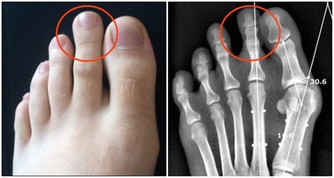

這個階段,女性會出現月經不調、潮熱盜汗、骨質疏鬆、失眠、精神暴躁等症狀,

更年期女性骨質流失相對來說比較嚴重,運動不僅能夠強身健體,也有補鈣的作用,